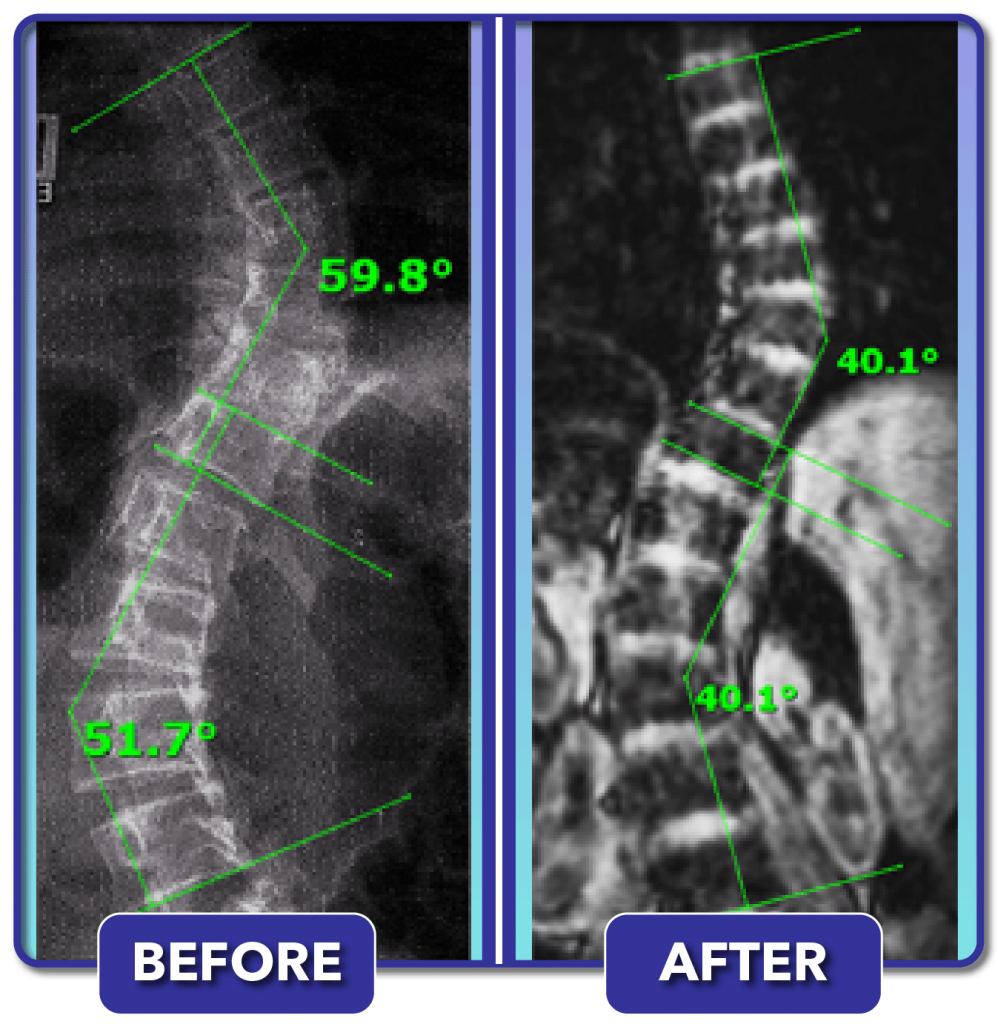

From scoliosiscenterofutah.com

Reduction of a severe scoliosis using scoliosis specific rehabilitation Can You Run After Scoliosis Surgery So that’s exactly what i do…! Patients face both physical and emotional. Can you exercise after scoliosis surgery? Patients should expect to follow plenty of dos and don'ts in the months after surgery that can help smooth their recovery, according to praveen kadimcherla, md, an. Yes, you can, although the more important question is how long you ought to. If. Can You Run After Scoliosis Surgery.